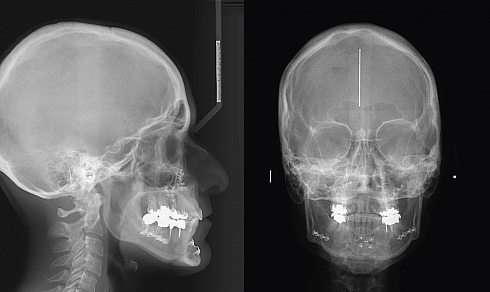

Planmeca ProMax 3D Classic Ceph – идеальная установка для получения трёхмерных изображений нижней и верхней челюсти, поэтому она отлично подходит для широкого спектра применения в имплантологии, челюстно-лицевой хирургии, пародонтологии, ортодонтии, исследовании височно-нижнечелюстного сустава, исследовании пазух, цефалометрии и пр. Данная гибридная установка объединяет в себе все функции классического ортопантомографа с цефалостатом и современные 3D-технологии для получения объёмных изображений.

- Основные панорамные и цефалометрические программы (в комплекте): Стандартная панорама взрослого, Стандартная панорама ребенка, — Боковой двойной ВНЧС, Двойной задне-передний ВНЧС, Задне-передний синус (прямой слой), Боковая и передне-задняя цефалометрические проекции, Проекция кисти.